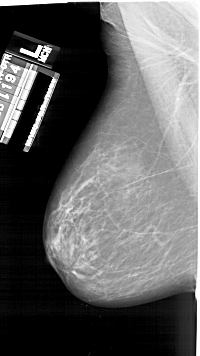

A_1925_1.LEFT_CC

LEFT_CC LINES 6061 PIXELS_PER_LINE 3616 BITS_PER_PIXEL 12 RESOLUTION 43.5 NON_OVERLAY